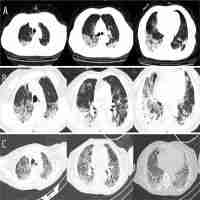

| Abstract | Here we report a critically ill patient who was cured of SARS-CoV-2 infection in Changsha, China. A 66-year-old Chinese woman, with no significant past medical history, developed severe pneumonia-like symptoms and later diagnosed as severe COVID-19 pneumonia. Within two months of hospitalization, the patient deteriorated to ARDS including pulmonary edema and SIRS with septic shock. When treatment schemes such as antibiotics plus corticosteroids showed diminished therapeutic value, hUCMSCs therapy was compassionately prescribed under the patient’s consent of participation. After treatment, there were significant improvement in disease inflammation-related indicators such as IL-4, IL-6 and IL-10. Eventually, it confirmed the therapeutic value that hUCMSCs could dampen the cytokine storm in the critically ill COVID-19 patient and modulated the NK cells. In the continued hUCMSCs treatment, gratifying results were achieved in the follow-up of the patient. The data we acquired anticipates a significant therapeutic value of MSCs treatment in severe and critically ill patients with COVID-19, while further studies are needed. |